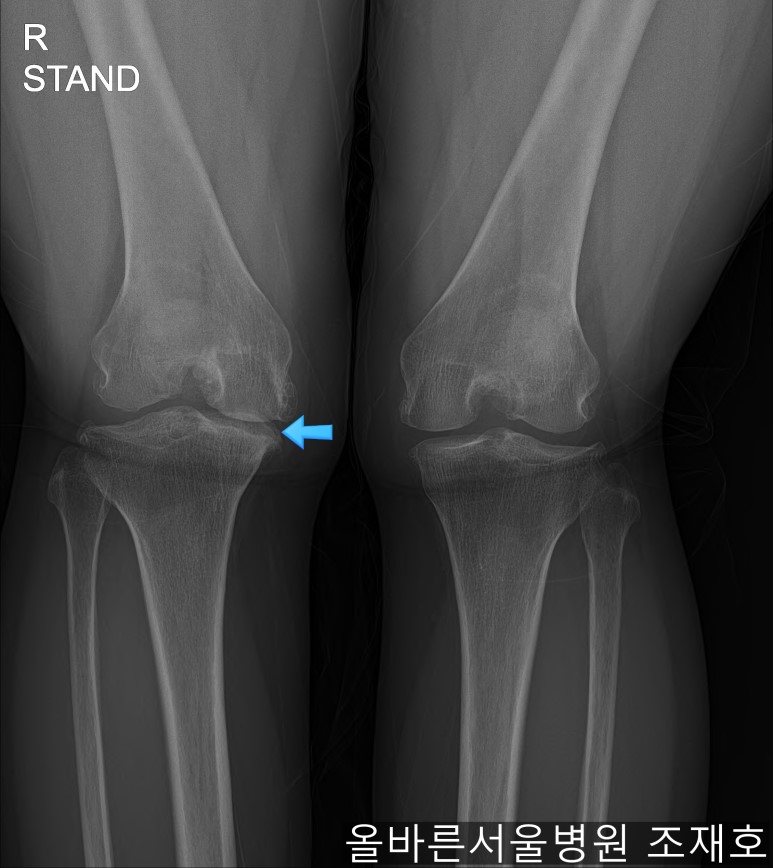

某患者,女,54岁,大面积软骨损伤,伴随内翻畸形,实施非切开CARTSTIEM手术及胫骨近端外翻截骨术,2、3年前右侧膝盖开始疼痛,在其他医院做了两次关节镜手术后疼痛加剧,膝关节变形严重遂到本院接受治疗。

仅通过放射线片子观察到:右膝由于炎症严重,内侧胫骨及股骨已接触在一起,向内测严重变形。

如果通过X光片也观察到相同的病症,可以判断内侧关节的软骨大部分都损伤了。

观察膝盖下肢排列的扫描图像可看到右腿严重变形,身体中心向内倾斜。